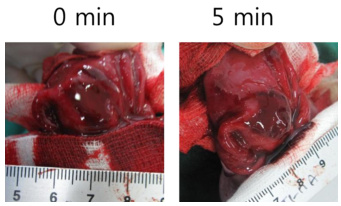

- 处死与取胃:在灌胃后预定的时间点(如大鼠1小时后,小鼠30~60分钟后),通过颈椎脱臼法或其他合适的方法处死动物。然后迅速剖腹,结扎幽门和贲门,以防止胃内容物外溢。

- 胃组织固定与清洗:从动物体内取出胃后,立即注入甲醛溶液进行固定。固定时间一般为30分钟至1小时。之后沿胃大弯剪开胃壁,外翻胃组织,倒去内容物,并用生理盐水轻轻冲洗去胃内残渣。

- 观察与记录:在解剖显微镜下观察胃黏膜的溃疡损伤程度。溃疡长度大于1mm者测其长度,每1mm计为1分;宽度大于1mm者则计分加倍;若为小溃疡点计0.5分。将计分相加即为该动物的溃疡指数。

损伤评估:宏观观察胃黏膜出血、糜烂灶,计算溃疡指数(UI):溃疡长度>1 mm计1分,宽度>1 mm追加1分。组织学切片(HE染色)评估黏膜上皮脱落、炎性浸润及出血深度。